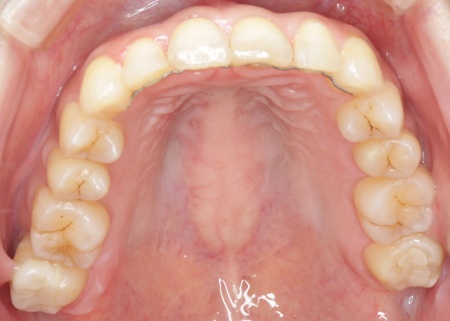

治療後

診断結果を踏まえ、まずはワイヤー矯正で歯並びと噛み合わせを整え、その後に形が変化している歯や劣化した詰め物を白いセラミック素材で作り直す治療計画を提案し、同意いただきました。 この治療方法であれば、歯を動かして噛み合わせの位置関係をしっかりと整えたうえでセラミックによる修復治療を行えます。また金属を使用しない白い素材を用いるため、見た目の違和感を抑えられます。 また、下の左右に半分埋まっている親知らず(第3大臼歯)があるため、矯正治療の際に抜歯する必要があることをお伝えし、ご了承いただきました。 まず親知らず2本を抜歯し、ワイヤー矯正治療から開始します。

矯正治療が終了したあと、セラミックによる修復治療へと移行しました。 さらにすり減って形が不揃いになっていた下中央の前歯2本には、ラミネートベニアと呼ばれる歯の表面に薄いセラミックの板を貼り付ける方法を用いて形を調整しました。 以上の工程を順に進め、すべての治療を終了しました。 |